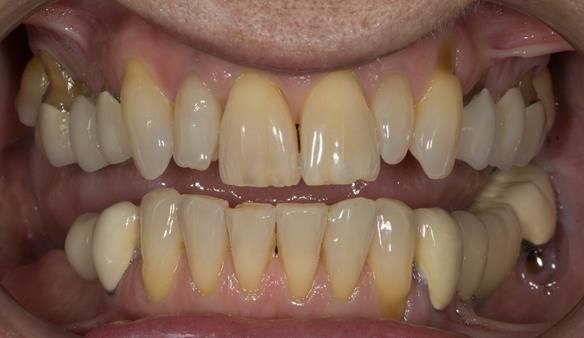

This newsletter describes in step by step detail Angela's transition through immediate partial dentures to crown supported definitive metal based dentures.

This 58 year old woman was referred to me by her general dental practitoner for treatment.

- Generalised Periodontitis; Stage 4, Grade C, Currently Unstable. Risk Factors: Type 1 diabetes. 16, 17 - hopeless prognosis. 14, 24, 26, 27, 34, 37, 44 - guarded prognosis

- Poor marginal fit and poor appearance of crowns and bridgework

- Yellowing teeth

The clinical situation and treatment process is shown in detail below with photographs. I (Finlay Sutton) provided the clinical work and Rowan Garstang provided the technical work.